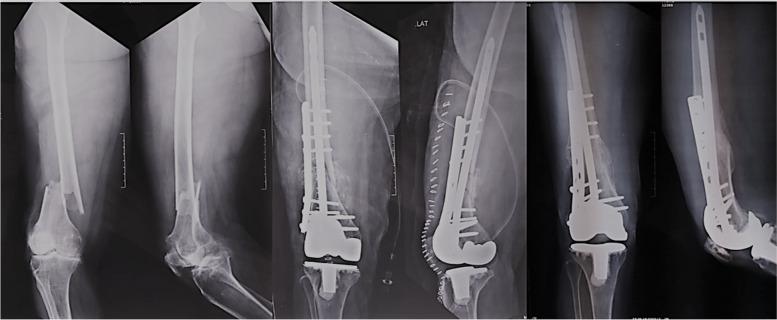

采用双重固定和全膝关节置换术治疗合并骨关节炎的髁上骨折的新型治疗方法的短期结果

Short-term results of a novel management of supracondylar fracture with coexisting osteoarthritis with bifold fixation and total knee arthroplasty.

Presence of supracondylar and periarticular femoral fracture with associated arthritis of knee poses a challenging situation to the orthopaedic surgeon. The results of fixation of fracture in osteoporosis are not very satisfactory and have complications. With fixation alone, they still cannot bear weight on affected leg due to severe disability of osteoarthritis. To make patient walk, conventionally three surgeries in the form of fracture fixation, removal of implant and total knee arthroplasty (TKA) needs to be done in staged manner. We propose a novel management in form of bifold fixation and simultaneous TKA.

METHODS

Eight cases (6 females, 2 males) of supracondylar femoral fractures with severe osteoarthritis of the knee and osteoporosis were primarily fixed with bifold fixation using SIGN nail ( www.signfracturecare.org ) and locking plate together with simultaneous total knee arthroplasty. There were five cases (2 males and 3 females) of grade 4 (Kellgren-Lawrence grading) osteoarthritis (OA) and three cases (all females) of severe rheumatoid arthritis (RA).

RESULTS

The mean age was 68 years and average time for full weight bearing was 6 days. Radiographic evidence of fracture union was achieved in 16.25 weeks. The mean Knee Society Score (KSS) and Western Ontario and McMaster Universities Osteoarthritis Index (WOMAC) score at 26 months was 83.13 and 22.13 respectively.

CONCLUSIONS

Single stage combined bifold osteosynthesis with interlocking nail and locking plate together with total knee arthroplasty helps in one time management of these difficult injuries. It is a cost-effective and economically sound option and gives excellent results with good patient satisfaction.